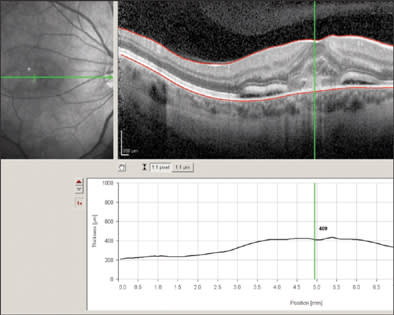

Figure 3. 3-D rendering of retinal topography with superimposed microperimetry threshold values in a case of central serous retinopathy. Image is sliced to reveal OCT cross-section showing focal macular detachment.

PHOTO COURTESY OF RICHARD B. ROSEN, MD

The Spectral OCT SLO Combination Imaging System (OPKO Health, Inc., Miami) performs a variety of scans while simultaneously producing a scanning laser ophthalmoscope (SLO) image for real-time registration. "It gives you perfect correspondence between the surface and cross-sectional anatomy, so you know exactly where the scan for the cross-section is taken," says Richard B. Rosen, MD, vice chairman and director of research, New York Eye and Ear Infirmary.

Clinicians can use blood vessels on the fundus image to align images, enabling them to obtain precise thickness maps incorporating a large number of cross-sections, Dr. Rosen says. Thickness maps can be rendered into 3-dimensional images, so that clinicians can scan through the retinal thickness map and view the OCT images beneath.

Thickness maps have a variety of configurations, Dr. Rosen says, corresponding to the ETDRS, showing critical target areas for treatment. "You can also overlay onto these thickness maps a whole system of microperimetry," he says. Using microperimetry, which is available as an add-on feature, the clinician can match a point of reduced sensitivity with OCT findings at the same point, for example.

In next-generation OCT advances, Dr. Rosen explains, the system will display letters for patients to read, correlating visual acuity with specific areas on the retina. He believes this will be especially useful for patients with severe vision loss. In patients with finger-counting or hand-motion vision, ophthalmologists often believe it is not worthwhile to treat the patient extensively, according to Dr. Rosen. "But oftentimes those patients have areas of the retina where they can still see letters and make out details, and so it may be useful for them to undergo a treatment to make use of that part of the retina." This software is under investigation, as is potential software for drusen analysis, he says.